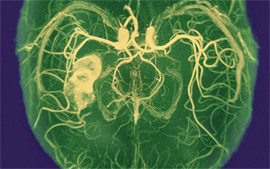

Охолодження мозку людей, які щойно перенесли інсульт, може врятувати життя |

У пілотних дослідженнях було показано, що зниження температури тіла пацієнта до 35 градусів Цельсія відразу після інсульту не менш ефективне, ніж тромболітична терапія, — воно покращує стан від семи до восьми відсотків пацієнтів, повідомляє The Daily Telegraph із посиланням на дослідження вчених Единбурзького університету, зазначає портал «Медновості».